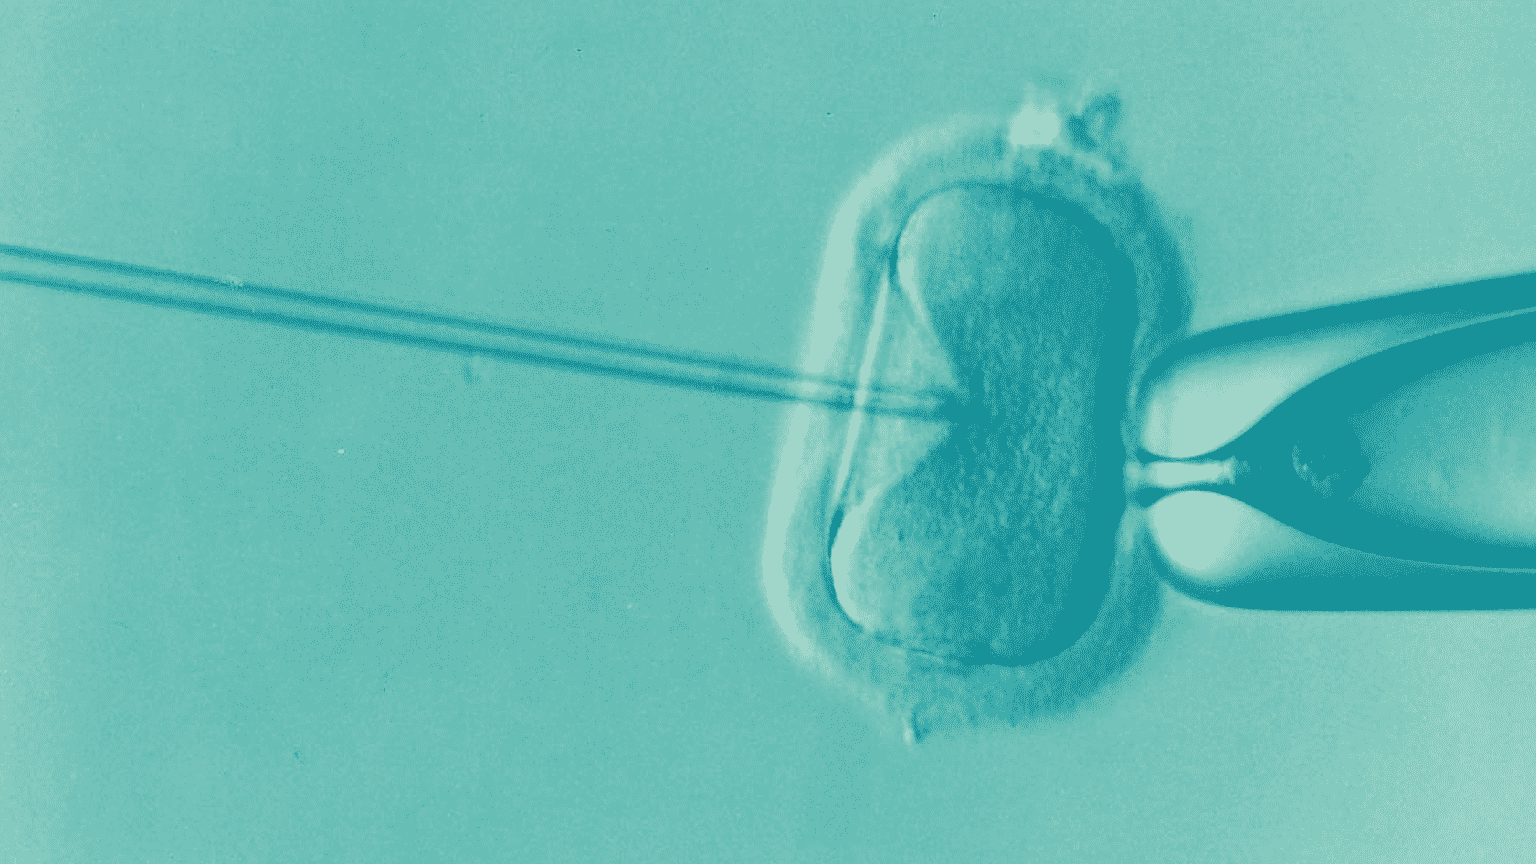

Everything you need to know about IVF procedure with Egg donor